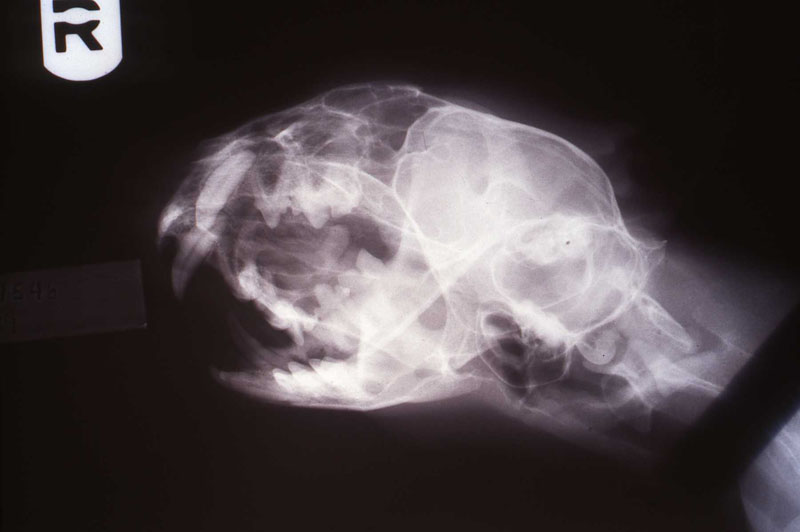

An 18 month old, 7.5 kg , female caracal (Caracal caracal caracal) new to the Milwaukee County zoo collection presented with a fractured right maxillary canine tooth during routine quarantine examination. The canine tooth had approximately 3 mm of its tip fractured off, the pulp chamber was exposed, and the tooth was darkened due to degeneration of of the pulpal tissue, and induction of food debris. There was no sign of an external drainage tract lesion. Radiographic examination revealed the presence of a periapical lesion 6mm by 7mm in diameter. The extra-oral surgical approach was chosen to debride the periapical lesion, resect the apex, and perform a retrograde fill in conjunction with the coronal or oblique endodontic fill.

lnteroperative and postoperative radiographs were obtained to verify endodontic working length and extent of endodontic fill.

The animal was reimmobilized using either a similar anesthetic regimen, or ketamine 6mg/kg and medetomidine (Domitor©, Pfizer Animal Health) 37 mcg/kg I.M., at 3 weeks, 14 months and 29 months. A small scar, approximately 1x4 mm, remains present at the incision site. Radiographs taken at each recheck showed healing of the periapical lesion, and normal bone repair in the surgical site.